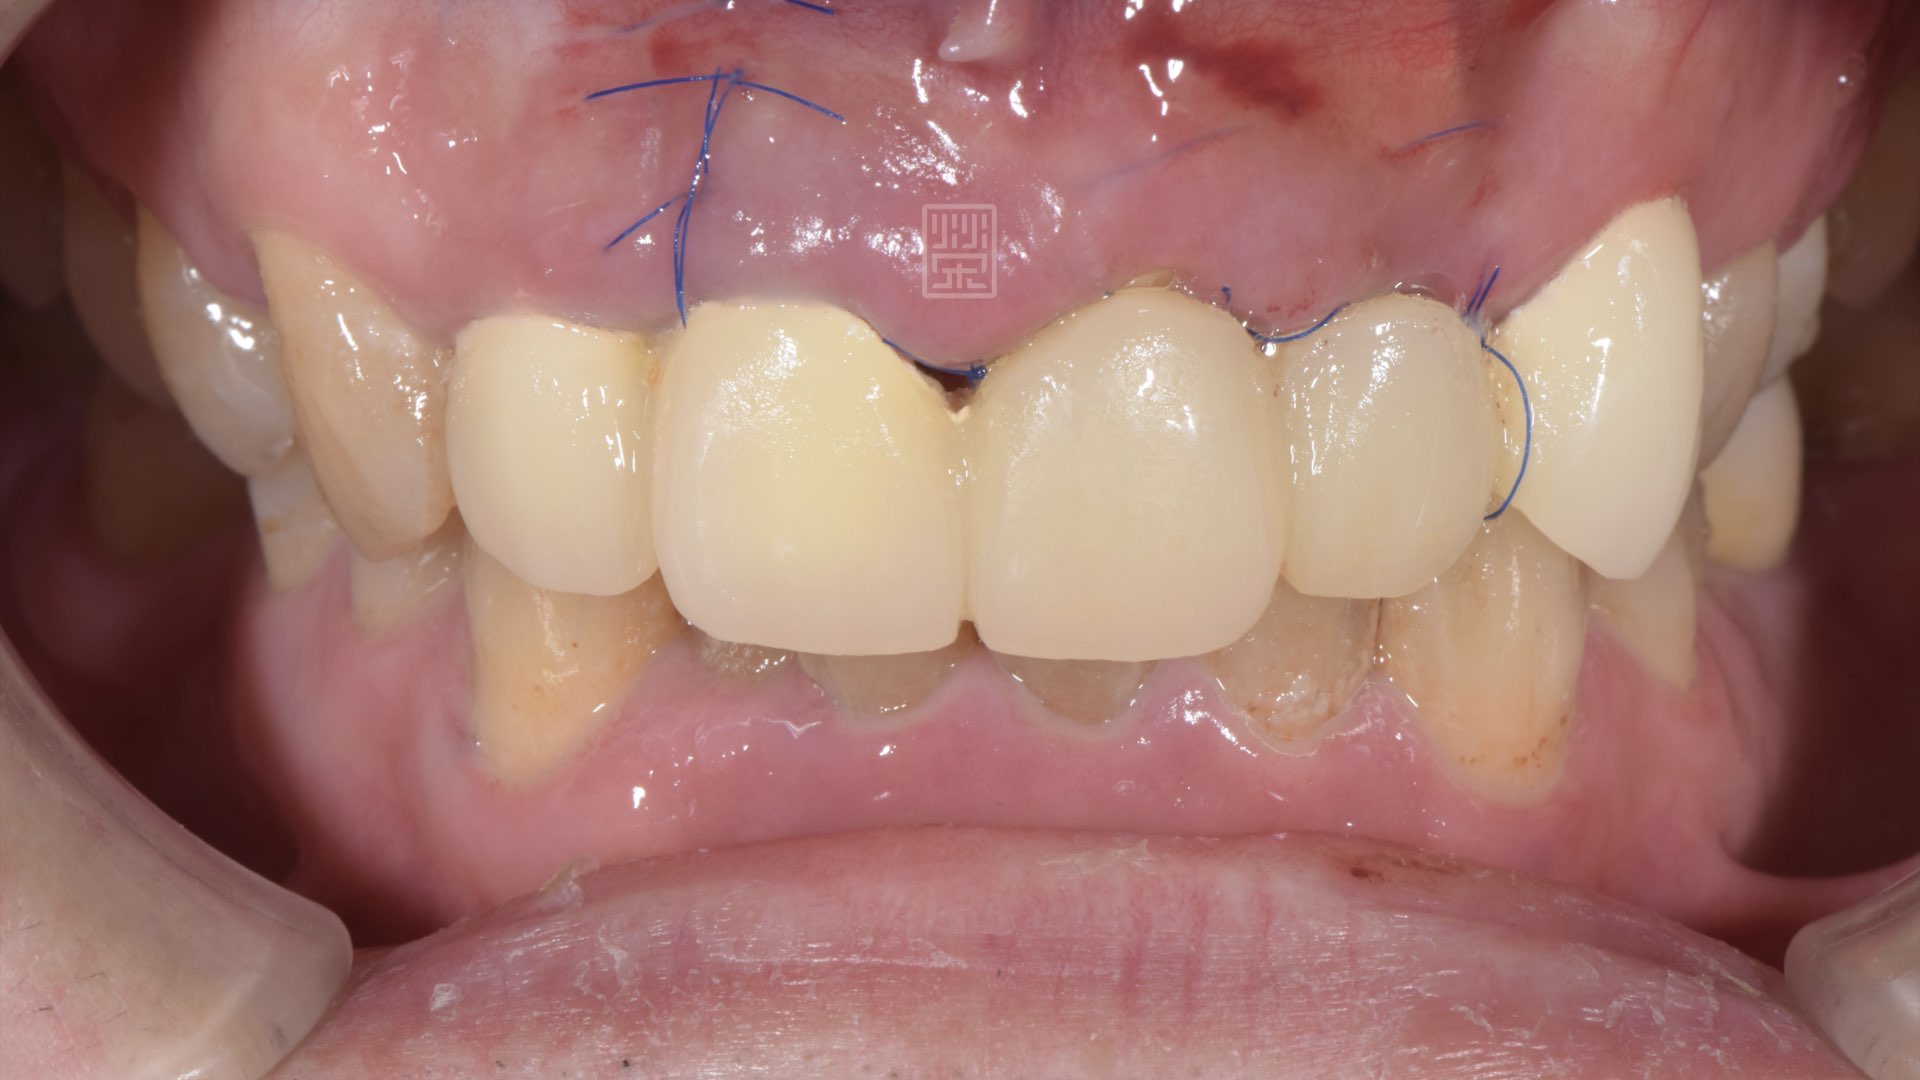

骨頭生長完成,植牙穩定後,接出臨時假牙

臨時假牙功能發音測試